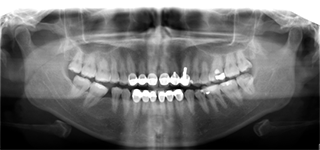

拍摄旧义齿口腔ct全景

接待董女士的是麦芽口腔的修复学专家熊少军专家,熊医生在得知董女士的情况后,详细地为她做了口腔检查。

考虑到董女士牙齿的特殊性和出现的问题,熊少军医生专门为她量身订做了一套麦芽数字化全瓷修复方案。